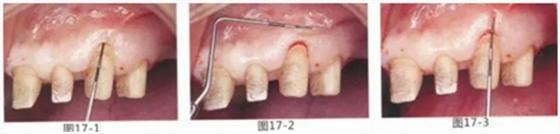

為了在左上1,2,3,4部位增加附著齦,左上1,2部位用Apically Positioned Flap(齦瓣根尖側轉移),左上3,4部位用游離齦移植的病例

圖17-1~3 左上3的牙周袋探測值為3mm,角化牙齦寬度為2mm。也就是完全不存在附著齦,如果這種狀態(tài)下佩戴修復體的話,很有可能發(fā)生頸部暴露等問題。

圖17-4 左上1,2進行齦瓣根尖側轉移,左上3,4進行游離牙齦移植,在去除牙周袋的同時獲取附著齦。

圖17-5 牙周治療完成后的正面照。左上3,4部位處游離齦移植片的上端通過骨膜縫合固定在頰側嵴頂部。這樣可以使其愈合效果與齦瓣根尖側轉移相同。